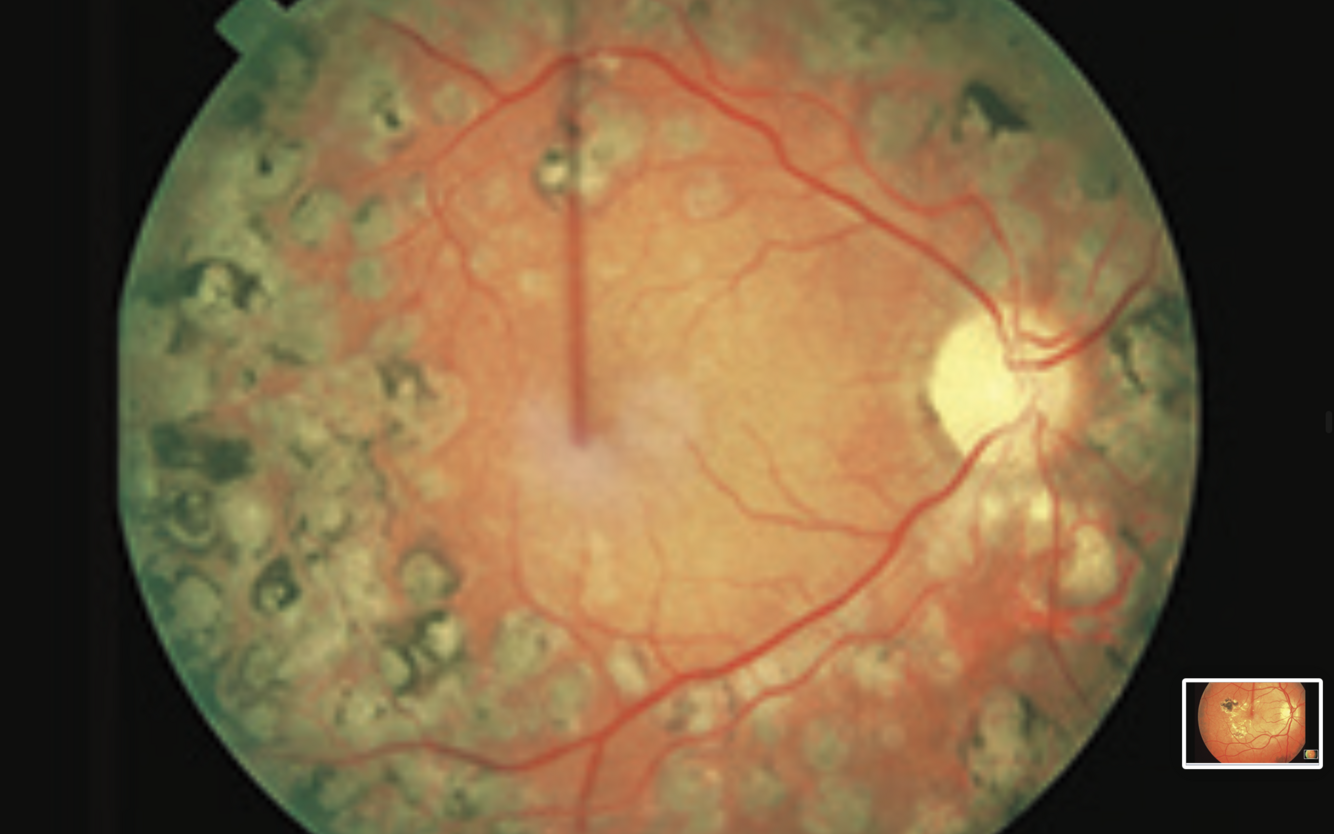

Pan retinal laser photocoagulation

- multiple laser scars with areas of hyperpigmentation

- will have reduced peripheral vision and a degree of night blindness